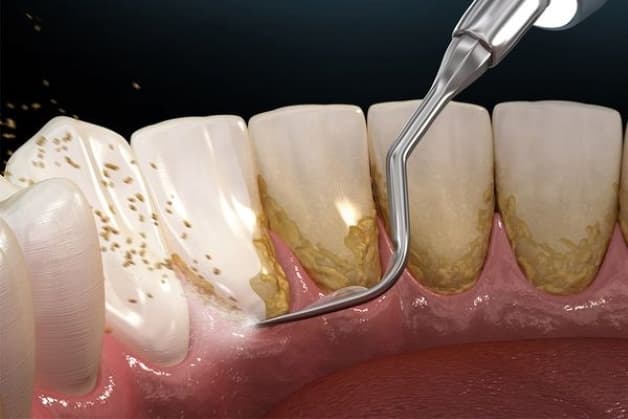

Lấy cao răng nên được thực hiện tại nha khoa uy tín để đảm bảo hiệu quả, an toàn

Trên đây là cách làm sạch cao răng tại nhà thường được áp dụng. Tuy nhiên theo nhiều chuyên gia khuyến cáo ta vẫn nên thực hiện lấy cao răng tại các nha khoa uy tín. Như vậy vấn đề hiệu quả và an toàn sẽ được đảm bảo hơn.